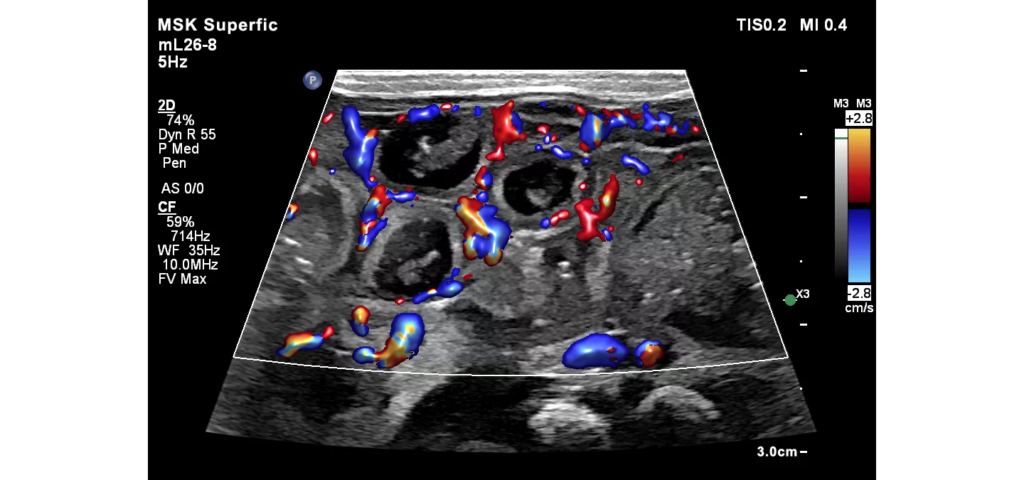

Philips EPIQ Elite ultrasound features an exceptional level of clinical performance, workflow, and advanced intelligence to meet the challenges of today’s most demanding practices. The EPIQ Elite platform brings ultimate solutions to ultrasound, with clinically tailored tools designed to elevate diagnostic confidence to new levels.